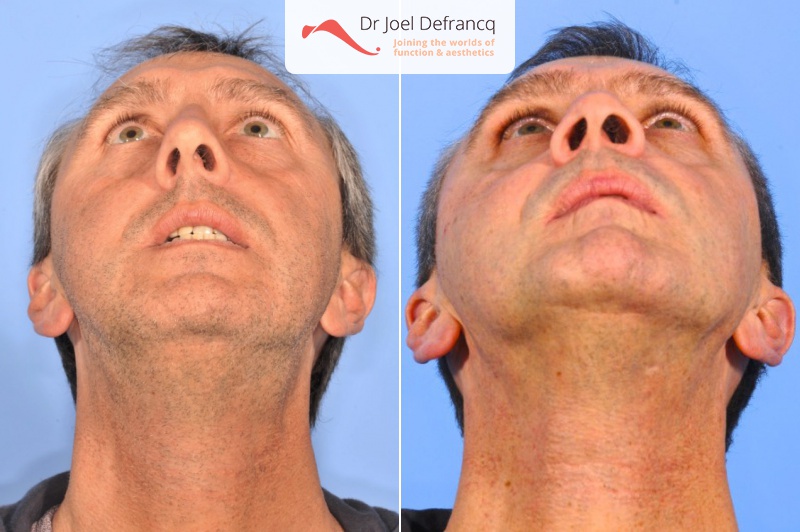

Jhonny: Kleine onderkaak, te kleine en te korte bovenkaak,

Diagnose van het gezicht

- Te kleine onderkaak (Overbeet)

- Te kleine bovenkaak

- Te kort gezicht

- Te korte bovenkaak

- Gekanteld beetvlak

Kaakchirurgie

- Verlenging onderkaak (BSSO)

- Verlenging bovenkaak (Le Fort I)

- Kinchirurgie

- Verbreden bovenkaak (Smile distractor)

Esthetische chirurgie

- Jukbeen augmentatie